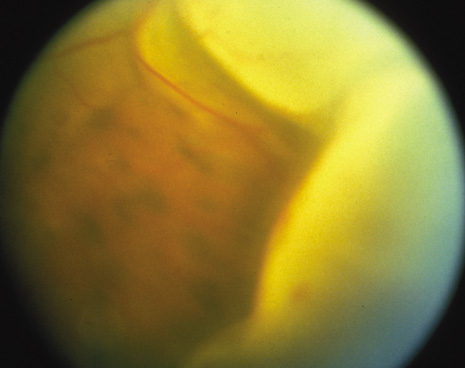

The onset of the disease is insidious. The injured eye becomes painful and photophobic, and visual acuity is diminished. The uninjured (sympathetic) eye then follows a similar course. On ocular examination, the injured eye shows persistent low-grade uveitis despite the healing wound. Characteristic bilateral panuveitis can be recognized by “mutton-fat” keratic precipitates, ciliary flush, aqueous cell and flare, posterior synechiae, vitreous cells and haze, choroidal thickening and infiltration, and optic nerve head edema. The presence of small, yellowish-white inflammatory infiltrates, 60 to 700 μm in diameter, at the level of the retinal pigment epithelium (Dalen-Fuchs nodules), but more commonly located at the midperiphery, is pathognomonic of SO (Fig. 1). In severe cases, rubeosis iridis, cataracts, pupillary membrane formation, and exudative retinal detachment can occur. Chorioretinal scarring may eventually form, and the eyes may become phthisic.1,40–42

Fig. 1. Multiple subretinal and choroidal infiltrates seen in the midperiphery of a patient with sympathetic ophthalmia.